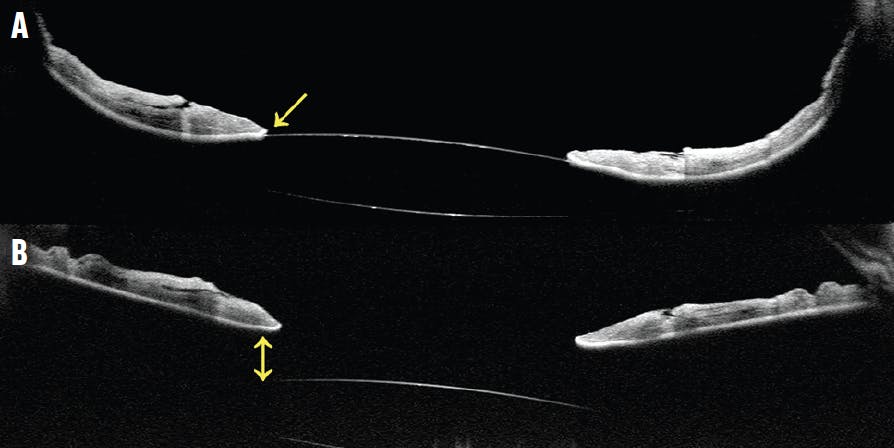

Reverse pupillary block (RPB) is an uncommon complication that can lead to elevated IOP, iris-optic capture, IOL instability, and refractive change. The mechanism of RPB is unclear, but a flaccid iris may prevent aqueous humor flow and cause a reverse pressure gradient.7,8 In patients without an existing PI who develop RPB during the postoperative period, an outpatient laser PI can be performed to break the RPB and reestablish the proper IOP gradient (Figure 3). Patel et al demonstrated that the rate of RPB decreased from 3% to 0.4% with intraoperative PI, and they recommended performing a prophylactic PI in all cases of sutureless intrascleral fixation.4

<p>Figure 3. This patient with a sutureless intrascleral-fixated three-piece IOL presents with elevated IOP and RPB. The anterior segment OCT shows a hyperdeep anterior chamber with IOL touch (single arrow) from a posteriorly bowed iris (A). Immediately following outpatient PI, OCT imaging shows release of the IOL touch (double arrow) and flattening of the iris (B).</p>

Figure 3. This patient with a sutureless intrascleral-fixated three-piece IOL presents with elevated IOP and RPB. The anterior segment OCT shows a hyperdeep anterior chamber with IOL touch (single arrow) from a posteriorly bowed iris (A). Immediately following outpatient PI, OCT imaging shows release of the IOL touch (double arrow) and flattening of the iris (B).